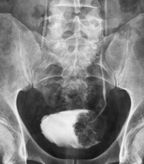

Large polypoid mass in the urinary bladder